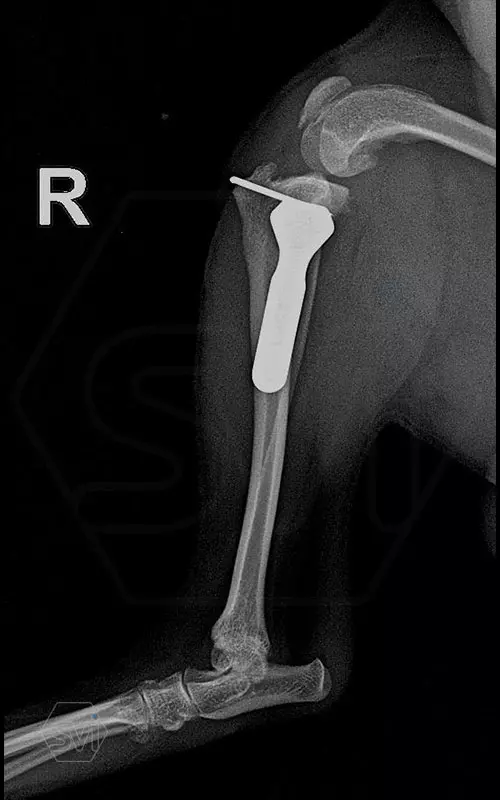

Introducing the TPLO-M „terraced” plate family from Smartvetimplants.com

In small dogs, medial patella luxation (MPL) and the rupture of anterior cruciate ligament (RACL) often occur simultaneously. During the surgical procedure, the joint must be stabilized and the patella fixed in the middle axis at the same time.

The solution of Smatvetimplants is the TPLO-M plate family with terrace:

Mini TPLO-M plate:

non-locking, symmetrical, with 2.2 mm terrace (degree of shift), for standard 2.0 mm AO cortical screws (1.5 and 2.4 mm screws can also be inserted), material steel. Optimized for R12 blades.

Between October 2020 and December 2021, we performed 19 TPLO-M surgeries at the Animal Hospital in Nyíregyháza,: 16 times used the mini (2.0 R12) and 3 times the small (2,4 R15) TPLO-M plate.

The experience is very encouraging, we find the system and plates suitable for the simultaneous treatment of MPL and RACL. ( in case of 4/4 pat. lux. also). We will back soon with details.